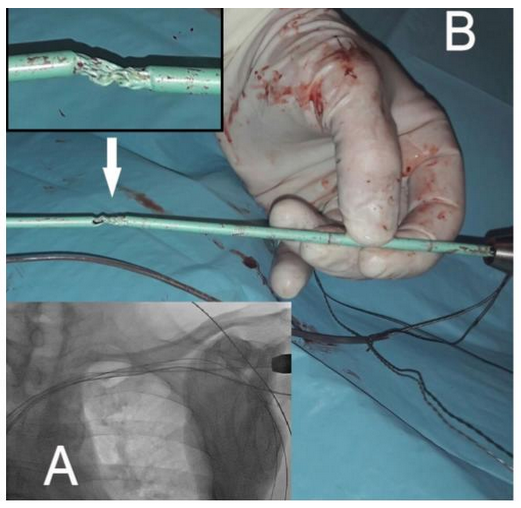

When in the proximal part of intavenous lead, the advancement of the dilator seemed able to disrupt the endovascular fibrosis which offered a moderate resistance to sheath advancement (Figure 3 - Panel A) with apparent preserved rotational maneuverability. When removed, the sheath appeared markedly damaged (Figure 3 - Panel B) in the middle part. A further mechanical stress could have led to a complete sheath fracture with losing of its distal part inside the vein with dramatic consequences for the patient. A new polypropylene dilator sheath was then used and the procedure was successful accomplished.

Figure 3 Panel A: Fluoroscopic control during dilator sheath advancement. Panel B: Dilator sheath dameged.